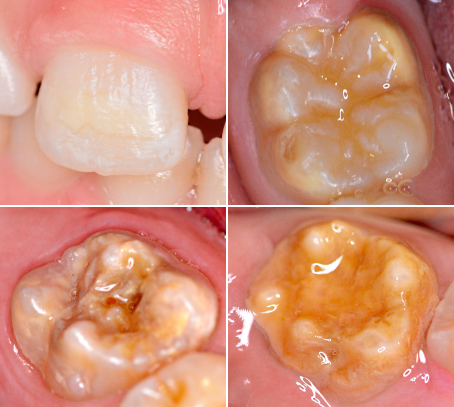

Wie erkennt man MIH?

Typische Anzeichen sind:

kreidige, matte Oberflächen

gelbliche bis bräunliche Verfärbungen

Je dunkler und ausgedehnter der Defekt, desto weicher ist der Zahnschmelz. In schweren Fällen kann es zum Abplatzen oder Zerbröseln der Zahnsubstanz kommen – unabhängig von der Zahnpflege. Betroffene Zähne sind deutlich anfälliger für Karies und benötigen frühzeitig zahnärztliche Betreuung.